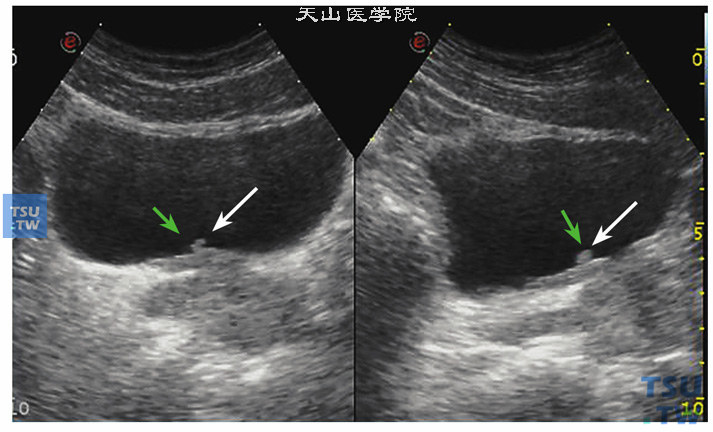

典型膀胱占位两例!(膀胱癌)

图片尺寸758x566